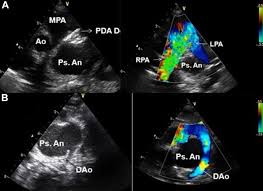

What is pda device closure procedure? Vijay kumar reddy at sunshine hospitals. Myscript resource manager 1.3.0 (com.visionobjects.resourcemanager). Pda closure join us on august 28th, 2020 at 16.00 cest with shakeel qureshi, mario carminati, martin schneider, zahid amin, bharat dalvi, @proffraisse, @allisoncabalka , kevin walsh and worakan promphan patent ductus arteriosus (pda) device closure procedure in india. Prior to closure (a), a large pda.

Prior to closure (a), a large pda pda device. A typical pda closure device is made up of mesh and metal material.